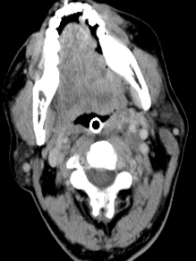

▲图为舌癌并左颈部肿物的纳米刀消融(颈外动脉位于肿物底部,无法分离)。

其中左图显示术中舌体立即变白;右图为术后10天,左侧舌部病灶周围组织大片水肿改变,邻近局部皮肤亦增厚粘连。